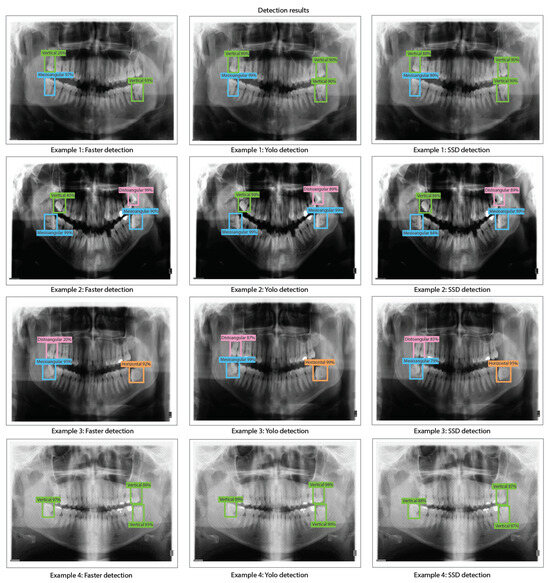

- We train, validate, and test DL-based object detection algorithms based on the You Only Look Once V2 (or YOLO V2), Faster Region-Convolutional Neural Network (Faster R-CNN), and Single Shot Multi-box detector (SSD). We compare the performance of each object detection model by using ResNet-18, ResNet-50, and ResNet-101 for the feature extraction stage of each detector.

- We present our results by using precision-recall curves in the proposed dataset. In addition, we evaluated bias, variance, overfitting, and underfitting for each model trained based on YOLO V2, Faster R-CNN, and SSD for the proposed dataset along with detection results and comparison tables of detection percentages.

- We obtained the best results for Faster R-CNN using ResNet-18 were reached in test 2 (training: 25%, validation: 24%, and testing: 39%). For YOLO V2 using ResNet-18, the best result is test 10 (training: 99%, validation: 90%, and testing: 96%). Finally, for the SSD model using ResNet-18, the best result was in test 12 (training: 87%, validation: 82%, and testing: 81%). This indicates that the best model for this experiment set is YOLO V2 using ResNet-18 with the hyper-parameter configuration of test 10. This model has a low bias and variance, demonstrating high generalizing capabilities (no overfitting) since the accuracy is barely reduced from training to validation and testing. We can observe the training, validation, and testing results for models obtained in tests 2, 10, and 12 in Figure 10, in which we present the precision-recall curves for such models.

- We obtained the best results for YOLO V2 using ResNet-50 in test 18 (training: 99%, validation: 89%, and testing: 95%). For the SSD model using ResNet-50, the best result was in test 9 (training: 88%, validation: 91%, and testing: 88%). This indicates that the best model for this set of experiments is YOLO V2 using ResNet-50 with the hyper-parameter configuration of test 18. This model has a low bias and variance, demonstrating high generalizing capabilities (no overfitting) since the accuracy is barely reduced from training to validation and testing. We can observe the training, validation, and testing results for models obtained in tests 11, 18, and 9 in Figure 12 in which we present the precision-recall curves for both models.

- We obtained the best results for YOLO V2 using ResNet-101 in test 11 (training: 99%, validation: 92%, and testing: 99%). For the SSD model using ResNet-101, the best result was in test 12 (training: 88%, validation: 90%, and testing: 89%). This indicates that the best model for this set of experiments is YOLO V2 using ResNet-101 with the hyper-parameter configuration of test 11. This model has a low bias and variance, demonstrating high generalizing capabilities (no overfitting) since the accuracy is barely reduced from training to validation and testing. We can observe the training, validation, and testing results for models obtained in tests 5, 11, and 12 in Figure 14 in which we present the precision-recall curves for both models.

- During the implementation of third-molar detection algorithms using different detection models and ResNet architectures, it can be observed that YOLO V2 is the model that stands out in terms of both accuracy and consistency during the training, validation, and testing stages. Therefore, the best results from our experiments were obtained by YOLO V2 using ResNet-18 (training: 99%, validation: 90%, and testing: 96%), YOLO V2 using ResNet-101 (training: 99%, validation: 92%, and testing: 99%), and YOLO V2 using ResNet-101 (training: 99%, validation: 92%, and testing: 99%), which indeed are very similar. These high accuracy results indicate that YOLO V2 is very effective for detecting third molar angles in our X-ray dataset distribution. On the other hand, the Faster R-CNN models with ResNet CNNs (ResNet-18, ResNet-50, and ResNet-101) possess underfitting problems for our X-ray dataset distribution. This might be because the Faster R-CNN is characterized by using an RPN (Region Proposal Network) stage. On the other hand, the SSD detection model has moderate accuracy across all ResNet architectures. Although SSD does not achieve the accuracy levels of YOLO V2, it produces reasonably consistent results, making it suitable for applications that require a balance of accuracy and detection speed (inference times less than 100 ms).

- Overall, we have demonstrated in this work that CNN-based object detection techniques can be used to detect third-molar angle detection based on Winter’s classification criterion. The categories that we detected are distoangular, vertical, mesioangular, and horizontal. To detect these categories, we have implemented several object detection methods, which are YOLO V2, Faster R-CNN, and SSD. Each of the mentioned object detection methods was trained by using ResNet-18, ResNet-50, and ResNet-101 as feature extraction methods, in which YOLO V2 with ResNet-18 obtained the best results (training: 99%, validation: 90%, and testing: 96%). These findings represent a promising solution for dentistry applications, such as improved diagnostic accuracy, more automated dental procedures, and even a possible training tool for educational applications. Moreover, we have presented a significant improvement compared to other works, that only train a single object detection method for different applications such as third molar detection and angle detection, tooth identification, caries detection, dental implant detection, and crown detection (see Table 7).